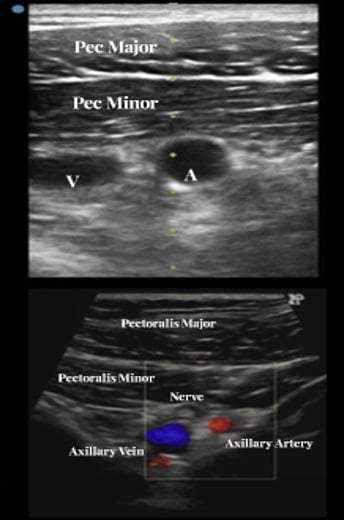

Step 4: ultrasound-guided puncture of the “sweet spot” (if used)

- Under ultrasound guidance, puncture the proximal axillary segment with a micropuncture needle using the standard Seldinger technique.

- Confirm true-lumen wire passage, then insert a small working sheath (Figure 7)

- If anything feels “not right” (wire resistance, unusual course), stop and confirm position with angiography via the safety channel.

Figure 7: Ultrasound identification of axillary artery, vein and nerve plexus